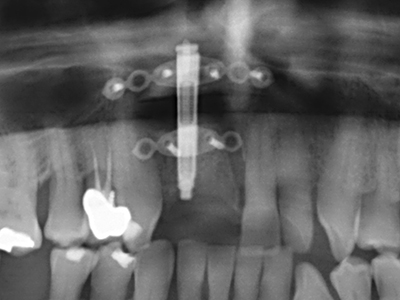

When surgical procedures are performed on bone in the immediate vicinity of sensitive structures such as blood vessels or nerves, rotary instruments pose a significant risk of iatrogenic injury. Piezoelectric devices can be helpful for preparation of bone covers and removal of hard tissue close to nerves, particularly for exposure of nerves after iatrogenic injury but also during nerve lateralization for resective and reconstructive procedures or implant placement (Fig. 17-20). Light contact between the piezotip and the nerve does not generally result in damage but proceeding incautiously with saw-like motions or attachments where a residual bone substrate remains may cause temporary or even permanent nerve damage. However, the risk of damage is considered to be substantially lower than when using saws or milling instruments (Pereira, Gealh et al. 2014).

As shown in the past, basically any bone surgery procedure represents a possible indication for piezo surgery. Thus preparation of the mobile segment in distraction osteogenesis (Fig. 23-25) and sandwich osteotomy uses special attachments without endangering the blood supply to the crestal section, which is essential for the success of both techniques (Gonzalez-Garcia, Diniz-Freitas et al. 2008).

Purely orthodontic indications include orthognathic surgery, genioplasty (Fig. 27-30) and orbital decompression in patients with advanced endocrine orbitopathy as a result of Basedow’s disease (Ponto, Zwiener et al. 2014). Piezo devices are also used in maxillofacial surgery and to remove tumours at the base of the skull in various hospitals.